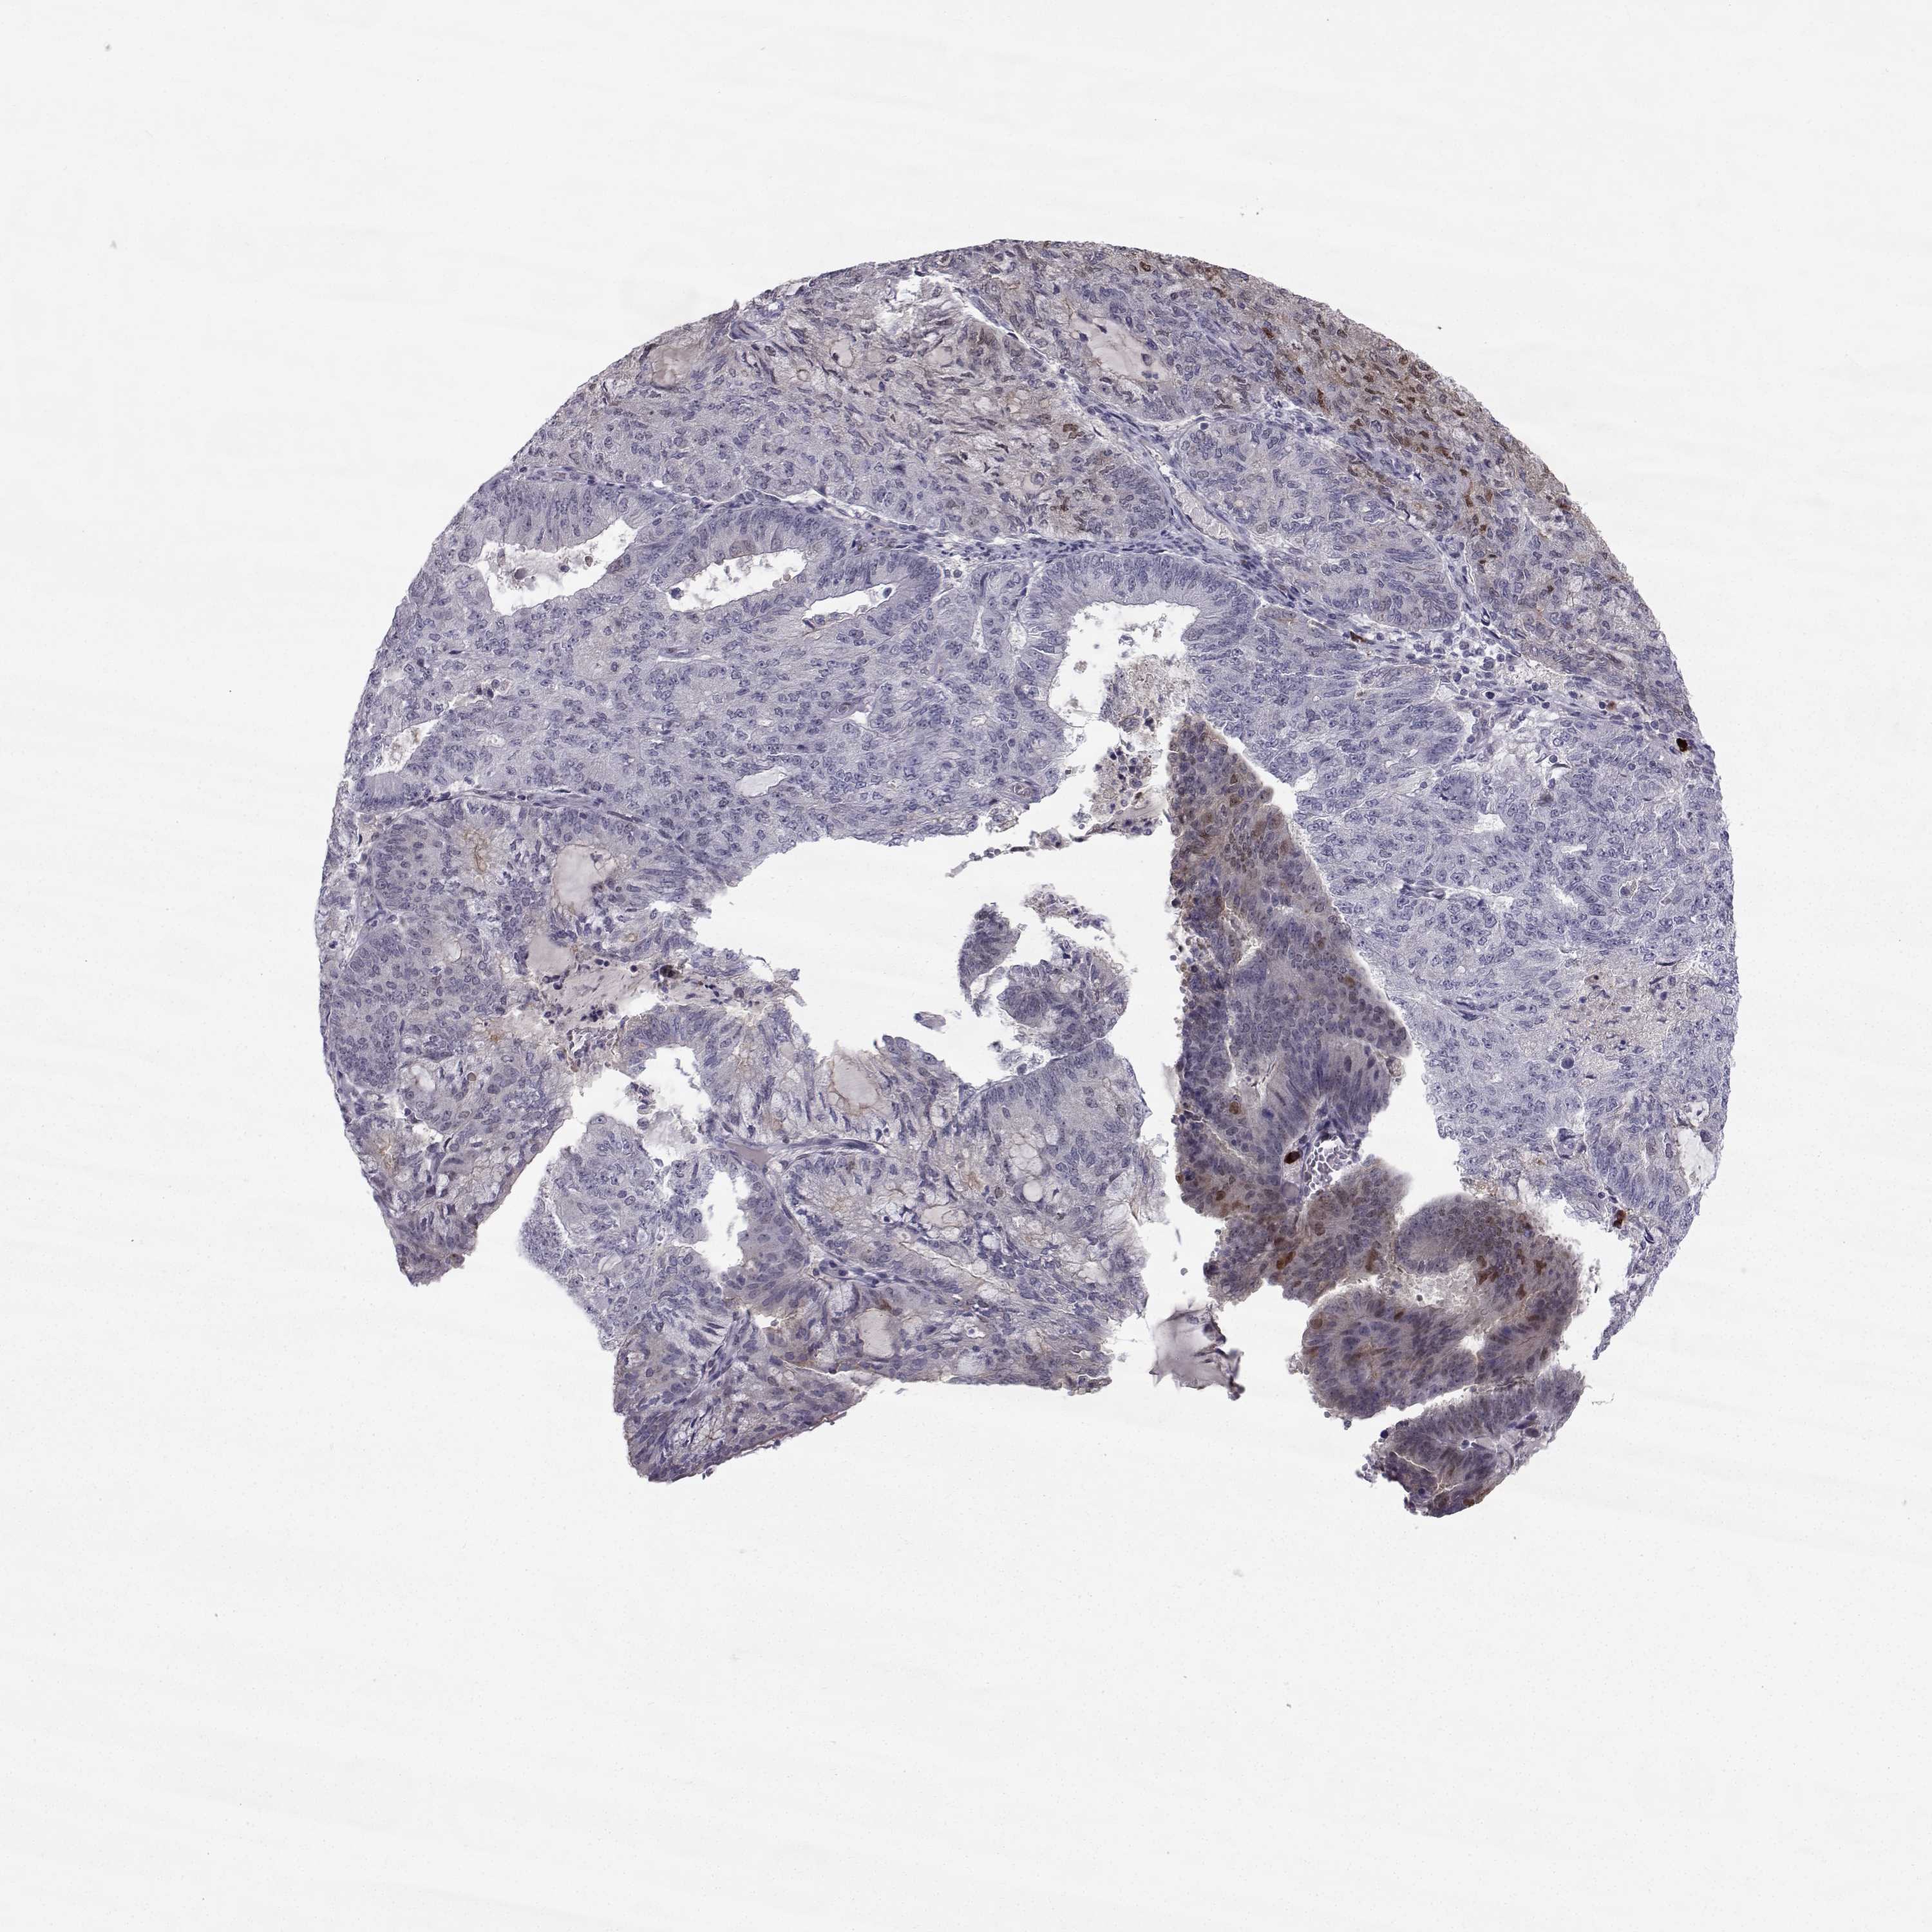

ENDOMETRIAL CANCER - Protein expressioni

A mouse-over function shows sample information and annotation data. Click on an image to view it in a full screen mode. Samples can be filtered based on level of antibody staining by selecting one or several of the following categories: high, medium, low and not detected. The assay and annotation is described here.

Note that samples used for immunohistochemistry by the Human Protein Atlas do not correspond to samples in the TCGA dataset.

Antibody stainingi

Antibody staining in the annotated cell types in the current human tissue is reported as not detected, low, medium, or high, based on conventional immunohistochemistry profiling in selected tissues. This score is based on the combination of the staining intensity and fraction of stained cells.

Each image is clickable and will lead to virtual microscopy that enables deeper exploration of all samples and also displays staining intensity scores, fraction scores and subcellular localization as well as patient and tissue information for each sample.

Antibody HPA066927

Staining

High

Medium

Low

Not detected

Intensity

Strong

Moderate

Weak

Negative

Quantity

>75%

75%-25%

<25%

None

Location

Nuclear

Cytoplasmic/membranous

Cytoplasmic/membranous,nuclear

Adenocarcinoma, NOS